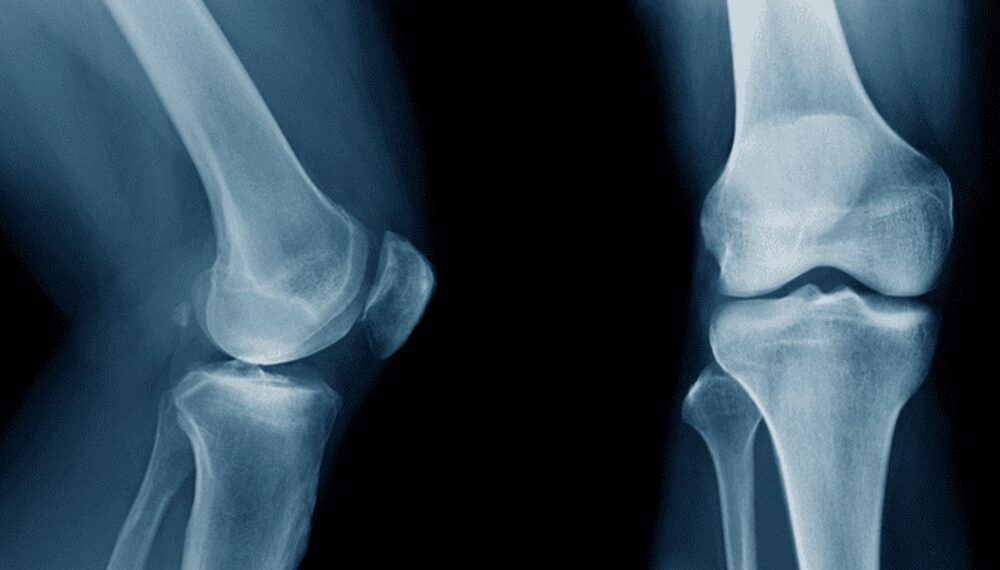

Researchers in China have developed a groundbreaking adhesive called Bone-02, capable of repairing fractures in as little as three minutes. This innovative bio-adhesive, which naturally dissolves...

Researchers in China have developed a groundbreaking bio-adhesive known as Bone-02, which has the potential to transform fracture treatment. This innovative material can repair bone fractures...